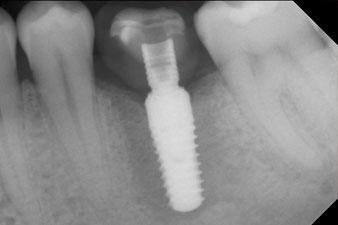

Abb. 10: Die Röntgenkontrolle zeigt die erfolgreiche Osseointegration und die spaltfrei verschraubte Krone.

Röntgenkontrolle